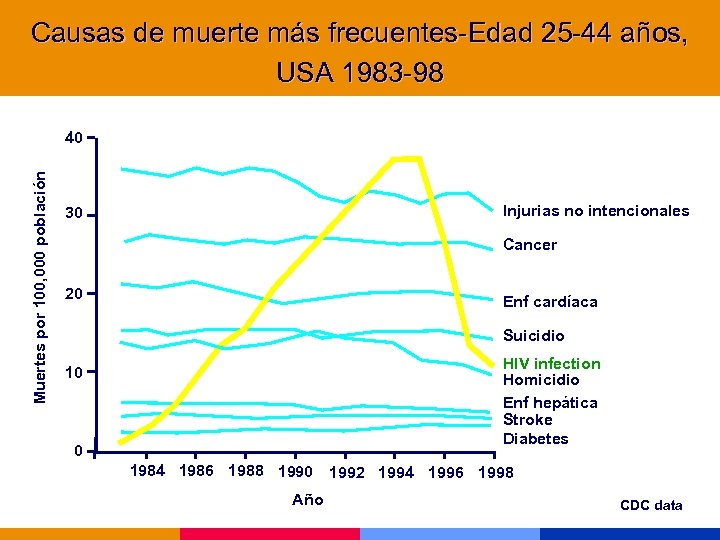

Causas de muerte más frecuentes-Edad 25 -44 años, USA 1983 -98 Muertes por 100, 000 población 40 Injurias no intencionales 30 Cancer 20 Enf cardíaca Suicidio HIV infection Homicidio Enf hepática Stroke Diabetes 10 0 1984 1986 1988 1990 1992 1994 1996 1998 Año CDC data

Causas de muerte más frecuentes-Edad 25 -44 años, USA 1983 -98 Muertes por 100, 000 población 40 Injurias no intencionales 30 Cancer 20 Enf cardíaca Suicidio HIV infection Homicidio Enf hepática Stroke Diabetes 10 0 1984 1986 1988 1990 1992 1994 1996 1998 Año CDC data